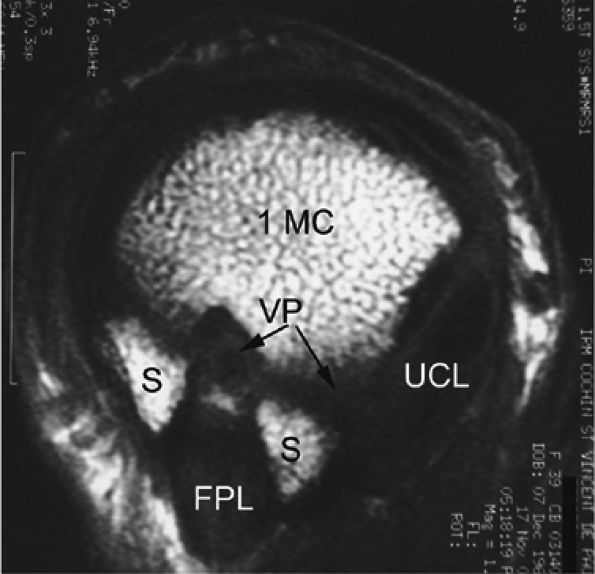

rotation. Stability is provided by the collateral ligaments, the volar plate, and musculotendinous elements. When the sesamoid bones are included in the volar plate, it is referred to as the volar complex (Fig. 11.4). On the medial aspect of the joint, the adductor pollicis is a strong insertion on the proximal phalanx and the volar plate, and contributes to the adductor aponeurosis. The ulnar collateral ligament (UCL) is covered dorsally by the adductor aponeurosis (Fig. 11.5).7,13

FIGURE 11.4 ● Volar complex of the thumb. Axial T1-weighted images. Sesamoid bones (S) are incorporated into the volar plate (VP). FPL, flexor pollicis longus; UCL, ulnar collateral ligament; 1MC, first metacarpal.

|